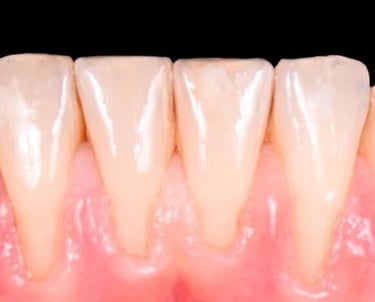

La ortodoncia corrige dientes mal posicionados y mejora la oclusión, favoreciendo tanto la estética como la salud bucal.

En IdenClinic tratamos a niños y adultos con distintos sistemas: brackets metálicos, estéticos y ortodoncia invisible.

Esta última utiliza férulas transparentes que pasan inadvertidas y alinean los dientes de forma progresiva y cómoda.

Analizamos cada caso con precisión digital y planificaciones personalizadas, logrando una sonrisa armónica, una mordida funcional y resultados estables sin comprometer la imagen del paciente durante el tratamiento.